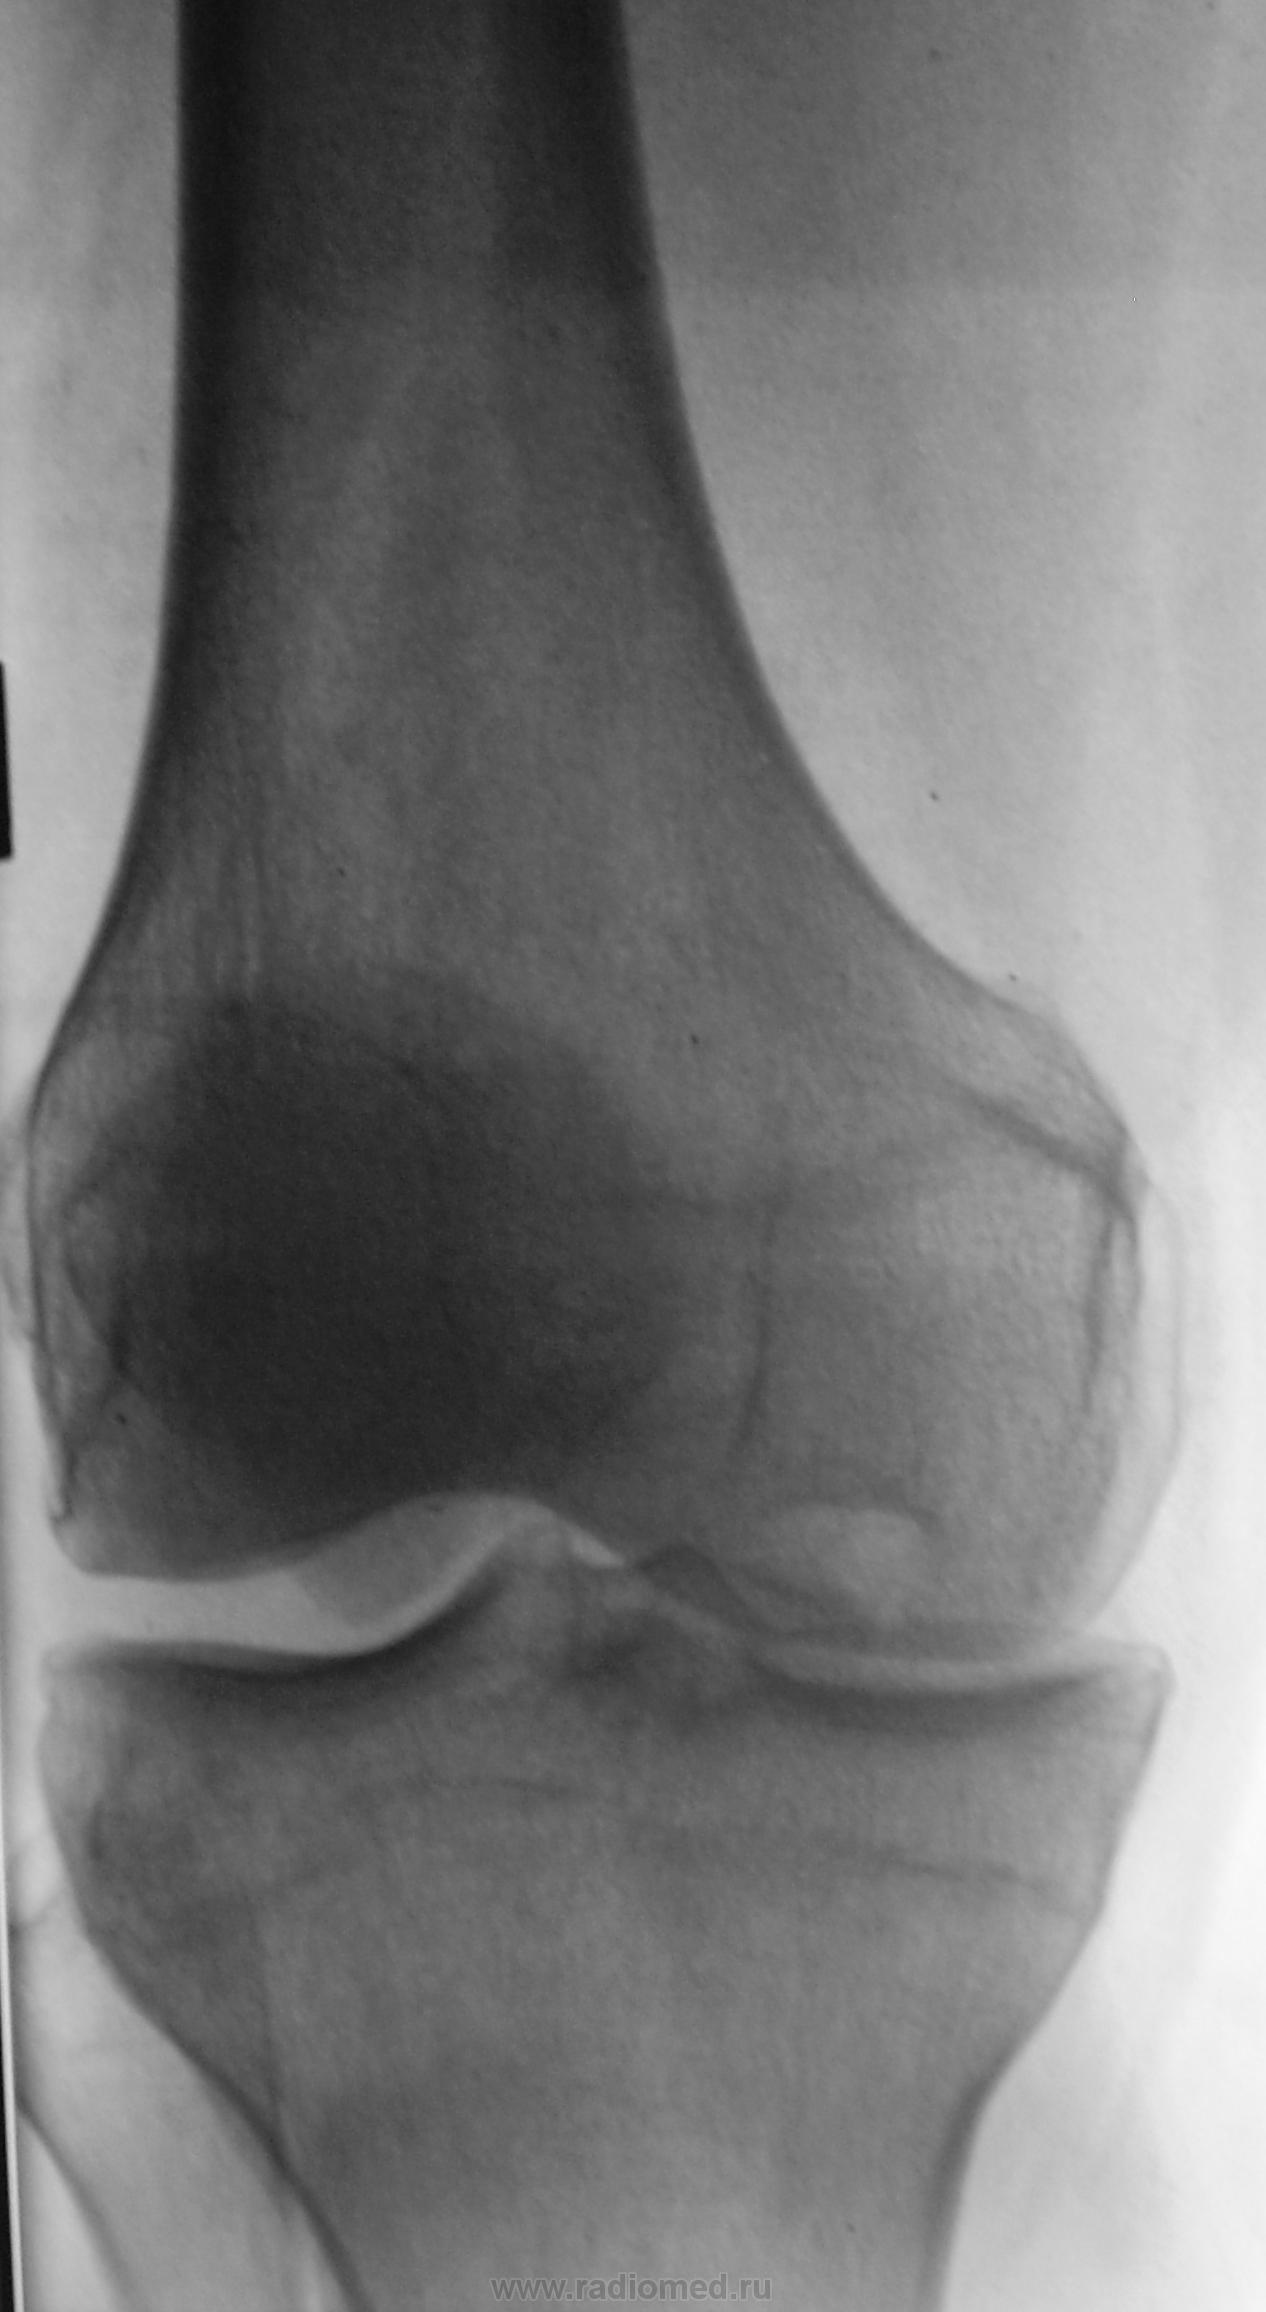

По поводу постоянных болей в коленном суставе пациент направлен на рентгенографию коленного сустава.

Практически "мой" случай, только мыщелок медиальный и гонартроз к 3-ей стадии приближается.

Остеоартроз, Кениг и неправильная прямая укладка.

Укладка правильная. Я тоже первый снимок забраковал, этот, второй делали при мне, правильная укладка, следовательно, ...выводы...

Ну, по поводу патологии по "типу Кенига" трудностей не возникает - законченный случай. Одностороннее сужение суставной щели без процесса остеофитообразования и субхондрального склероза (пока), лично я, связываю с функциональной несостоятельностью дополнительных компонентов сустава - мениска и связок. Возможно, у коллег будут другие мнения?